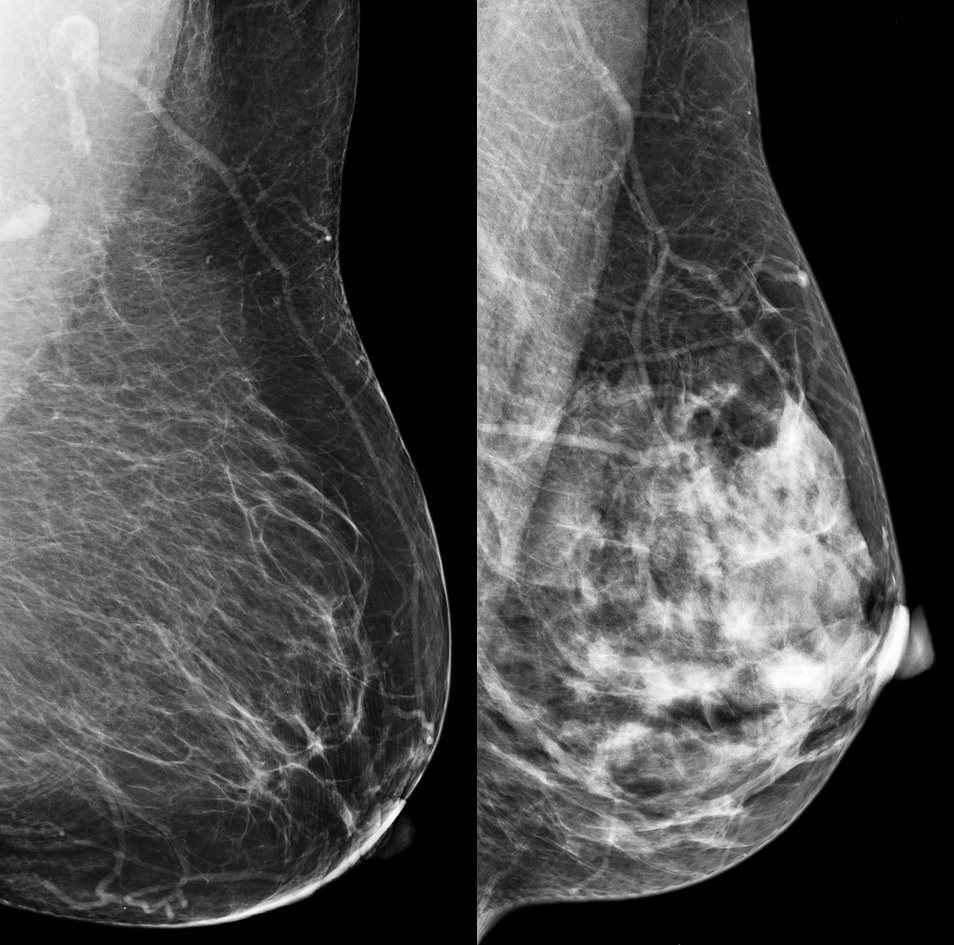

Dense breasts have more fibrous and glandular tissue that appears light grey or white on a mammogram while less dense breasts have more fatty tissue that appears dark. Dense tissue reduces the sensitivity of mammograms by masking the presence of tumours that also appear white, leading to underdiagnosis of breast cancer in those at the highest risk of developing it.